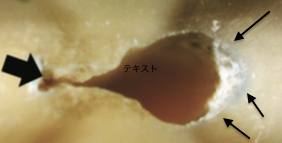

突然ですが下の写真、治療中の根管の断面の写真です。

上と下 どちらがより良い状態だと思いますか?

正解は『上』

上の写真は、SAFという器具を使って治療した後。

下の写真は、その他多くの手用ファイル、ロータリーファイルなどを使って治療した場合です。(歯の中の治療をする器具をファイルと言います。)

上はほとんど取り残しがないのに対して、下は矢印の部分を含めて取り残しがボチボチあります。

実はこの取り残しが、治療成績に関わってきます。

細菌の餌になってしまうから!!!!

この取り残しをいかに減らすか、少なければ少ないほど良いのです!

こんなことを言うと刺されるかもしれませんので小さい声で言いますが、この写真10分間、薬液を使用して治療した後です。SAFで治療を行ったものと比較すると、とれていないなぁと自分は思ってしまいます。これが、細菌の塊であるバイオフィルムであった場合、SAFでは3%程度まで減らせるのですが、従来型の器具では20%程度を取り残してしまいます。